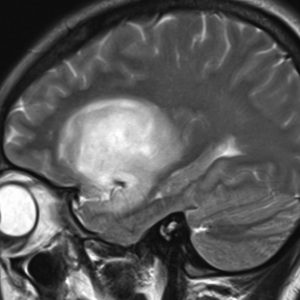

若い女性の左前頭葉から島回,側頭葉を侵す腫瘍で,てんかん発作で発症し,開頭生検 biopsy しました。

一部で,細胞密度が高く,核の腫大とクロマチンの増量,核間距離の短縮があり,核分裂像が認められ,MIB-1染色率が10%です。組織学的には退形成性乏突起膠腫グレード3とされました。

IDH変異あり,1P/19q欠失あり,ATRX変異なしです。

乏突起膠細胞系グリオーマなので,放射線治療の高線量領域はあまり広くとりません。

IMRT Simultaneous Integrated Boost (SIB)で,FLAIR高信号の領域に54グレイ27分割,周囲仮定浸潤領域 generous local areaに46グレイを照射しました。

テモゾロマイド75mg/m2を併用しています。

左の画像は放射線治療直後のMRIですが,すでに腫瘍の縮小がみられます。

テモゾロマイドの維持療法は,24コース 2年間行い,それ以降は無治療としました。

照射後7年の画像です。腫瘍は縮小したまま,患者さんは無症状で経過しています。